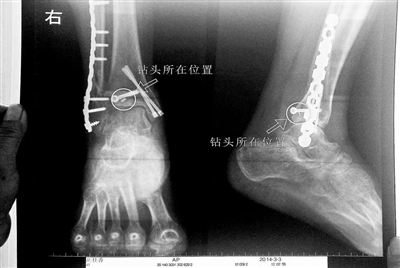

胡女士的腿部X光圖

看著X光片中自己腿內(nèi)的異物,胡女士就感到莫名的擔(dān)憂。胡女士于2013年3月在北京市豐臺(tái)區(qū)右安門醫(yī)院進(jìn)行了一次骨折手術(shù),術(shù)后醫(yī)生才發(fā)現(xiàn)手術(shù)時(shí)用來打眼用的鉆頭不慎遺留在了胡女士的骨頭中,并且無法取出。

近日,在豐臺(tái)區(qū)右安門醫(yī)院,北京青年報(bào)記者見到了胡女士,她走起路來顯得一瘸一拐,腿腳并不利索。在她帶來的X光片上,可以清晰地看到,有一個(gè)異物存在于腿內(nèi)部。

“我當(dāng)時(shí)就嚇蒙了,怎么會(huì)有一個(gè)鉆頭在骨頭里?”胡女士余悸未消地說,第二天拍攝的X光片顯示,2厘米左右的鉆頭遺留在她右腳腳踝上部的骨頭內(nèi)。

胡女士說,當(dāng)時(shí)旁邊的醫(yī)生勸慰自己,稱鉆頭留在腿里并不會(huì)有什么問題。出院后,胡女士每個(gè)月都會(huì)來醫(yī)院做復(fù)查,拍X光片。她說,每次都能夠清晰地看見自己骨頭里的那個(gè)明晃晃的“小東西”。